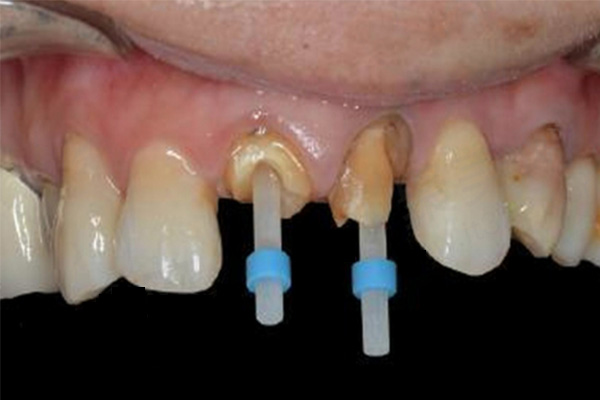

牙周炎的诊治并不总是成功的。在一些情况下,可能需要拔除很可能会受损的牙齿。然而,通过积极的诊治和预防,大多数人可以降低这种情况。那么佳洁士牙膏对牙龈炎牙周炎有效果吗?下文将带各位了解一下